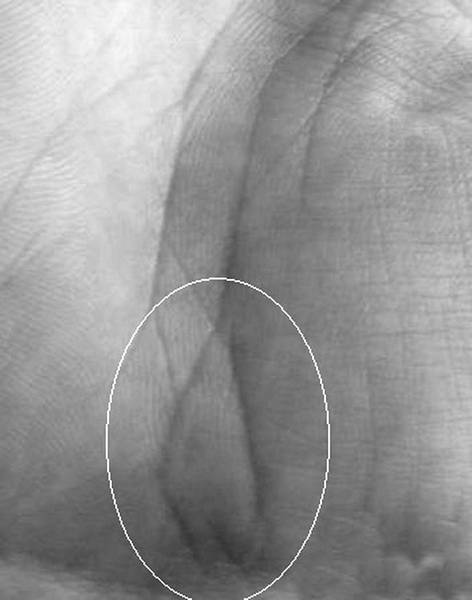

Рак простаты проявляется на ладони островом на холме Нептуна или Луны, выпускающим ветви в двух противоположных направлениях (рис. 1.97). На данной фотографии очень четко выражен знак простатита (в черном круге) и присутствующая «нить жемчуга» (в белом овале).

Рак средней доли левого легкого отображается двумя треугольниками расположенными внутри линии Жизни в проекционной зоне середины легкого, основания которых соединены между собой. На рисунке 1.99 приведена рука пожилого мужчины болеющего раком легкого последней стадии, ставшего следствием невылеченного в прошлом туберкулеза, где помимо общего признака (острова в нижней трети линии Жизни), выведен на ладонь и знак пневмонии (рис. 1.98), что в комплексе указывает на присутствие злокачественной опухоли левого легкого.